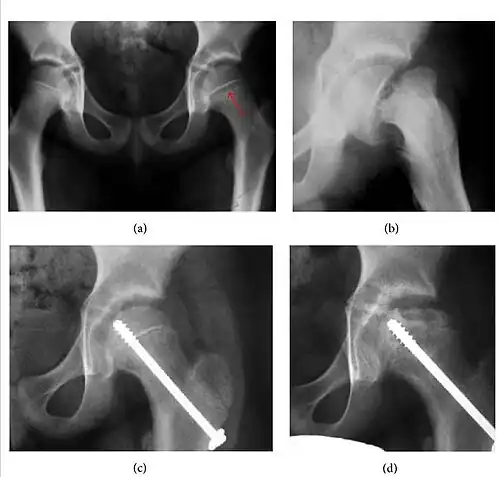

Slipped capital femoral epiphyses (SCFE)

Slipped capital femoral epiphyses (SCFE) usually affect 11- to 14-year-old adolescents (Figure 4). Radiographs may show widening and irregularity of the physis and posterior inferior displacement of the capital femoral epiphysis. On the AP view Klein’s line, tangent to the lateral aspect of the femoral neck, does not intersect the femoral head indicating that it is displaced. SCFE may compromise the blood supply to the femoral head and cause avascular necrosis, mainly when there is instability between the fragments.[1]